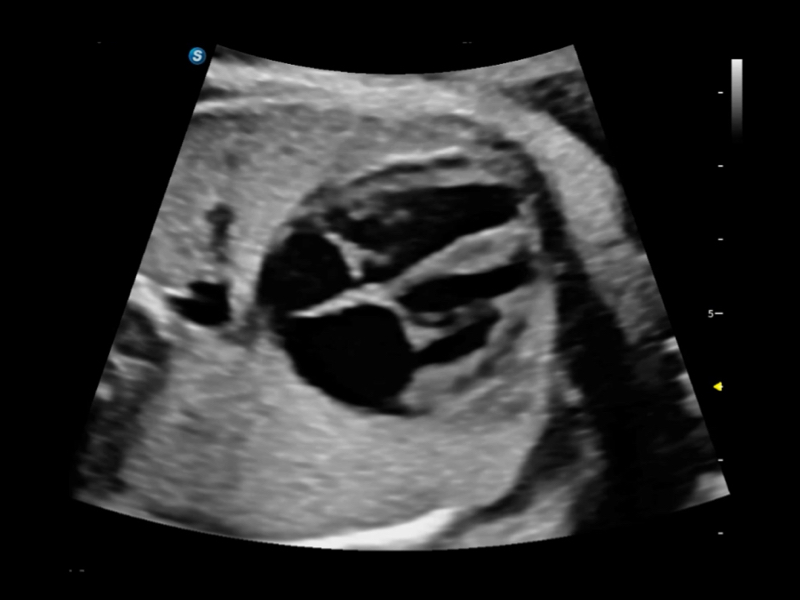

Exquisite Bildklarheit & Hämodynamik

Bildqualität steht stets im Zentrum verlässlicher klinischer Ergebnisse. Das S70i Fenix führt weiterentwickelte Schallköpfe mit herausragender 2D-Bildklarheit und hoher Farbsensitivität ein – für eine sicherere Beurteilung anatomischer Strukturen und pathologischer Veränderungen.

Premium-Wandlerlösung

Das S70i Fenix bietet eine Reihe fortschrittlicher, spezialisierter Schallköpfe, die Ultraschallexperten eine sicherere und effizientere Beurteilung anatomischer Strukturen ermöglichen – zur optimalen Unterstützung der Gesundheitsversorgung von Frauen.